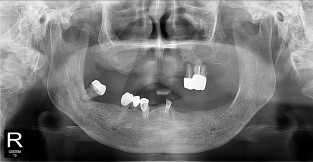

• 3

전체어금니

치료기간 : 2021-10-20 ~ 2023-08-31

1. 상기 x-ray 이미지 모두 동일한 해당 의료기관에서 진료한 환자입니다.

2. 상기 x-ray 이미지 모두 동일 인물의 것입니다.

3. 치료 전 이미지는 2021-10-20에 촬영했으며, 치료 후 이미지는 2023-08-31에 촬영하였습니다.

4. 상기 x-ray 이미지 모두 동일 조건에서 환자분의 동의를 받아촬영되었습니다.

* 임플란트 시술은 환자분의 상태(고혈압, 당뇨 등)에 따라 부작용이 있을 수 있으니, 반드시 전문의와 상담이 필요합니다.

* 임플란트 수술 부작용

: 수술 후 출혈, 교합, 통증, 붓기, 염증 등의 문제점이 발생할 수 있습니다.)